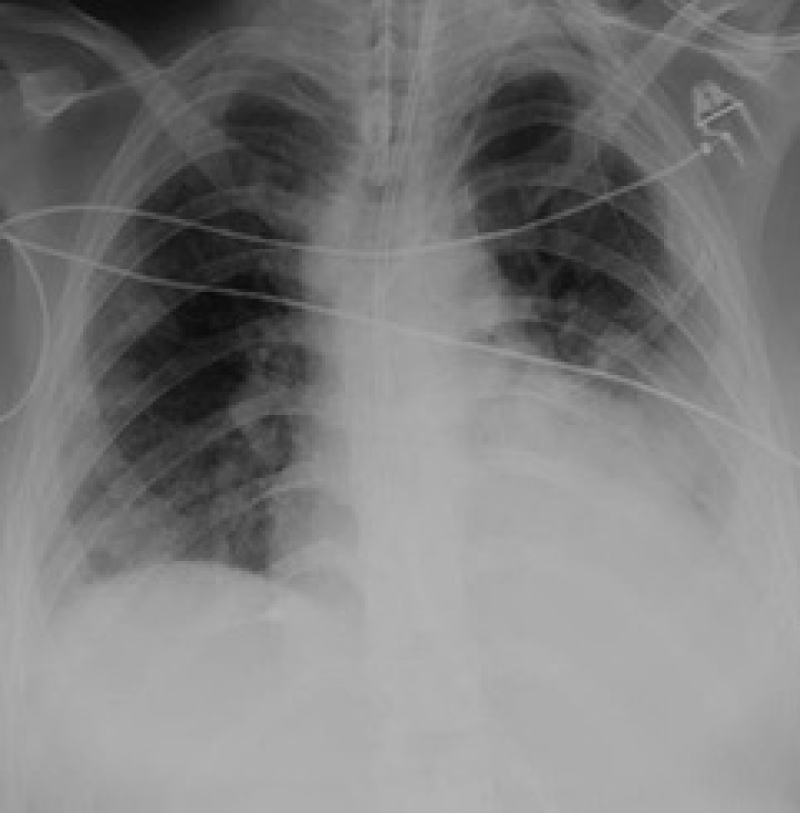

The case is presented of a 21-year-old female who initially presented with a sore throat and productive cough. She had previously been seen by a doctor in a primary care setting who diagnosed tonsillitis and commenced her on oral antibiotics. She had a background of recurrent chest and ear infections over the last few months, but no co-morbidities. She deteriorated significantly over the next twenty-four hours and was taken to her local Emergency Department (ED) by ambulance. Her presenting symptoms were vomiting, shortness of breath, and a cough productive of green sputum. On admission was found to be pyrexial, hypotensive, tachycardic and hypoxic. She was drowsy and had mottled extremities. A chest radiograph performed in the ED demonstrated left sided consolidation and right sided hydropneumothorax (Figure 1).

Figure 1: Chest radiograph on initial presentation to the local emergency department. View Figure 1